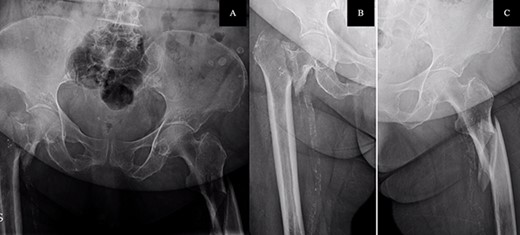

The postoperative course was satisfactory, without medical problems apart from non-complicated anemia (Hb 7.9 g/dl), solved with two units of red blood. On the first postoperative day, a radiographic control was completed (Fig. 3) and started early ambulation assisted by physiotherapists. On day twelve, she was transferred to a rehabilitation hospital. Outpatient follow-up visits evolving reasonably well. In the 6-month and 1-year check-up, the consolidation of the fracture was observed in the radiographic study (Fig. 4). No surgical wound problems, infections, or limping were identified. Anti-osteoporotic drug treatment was implemented along with an emphasis on a healthy diet with adequate protein intake and supplementation with calcium and vitamin D.

Postoperative anteroposterior pelvis radiograph: The left subtrochanteric fracture was first reduced with percutaneous assistance and synthesized with a reamed intramedullary long Gamma3 nail (340 mm,125°, Stryker®) with cephalic dynamic locking screw and two static distal locking screws. Then, after closed reduction, the right intertrochanteric fracture was fixated with a non-reamed short Gamma3 nail (180 mm,125°, Stryker®) with cephalic and distal dynamic locking screws.